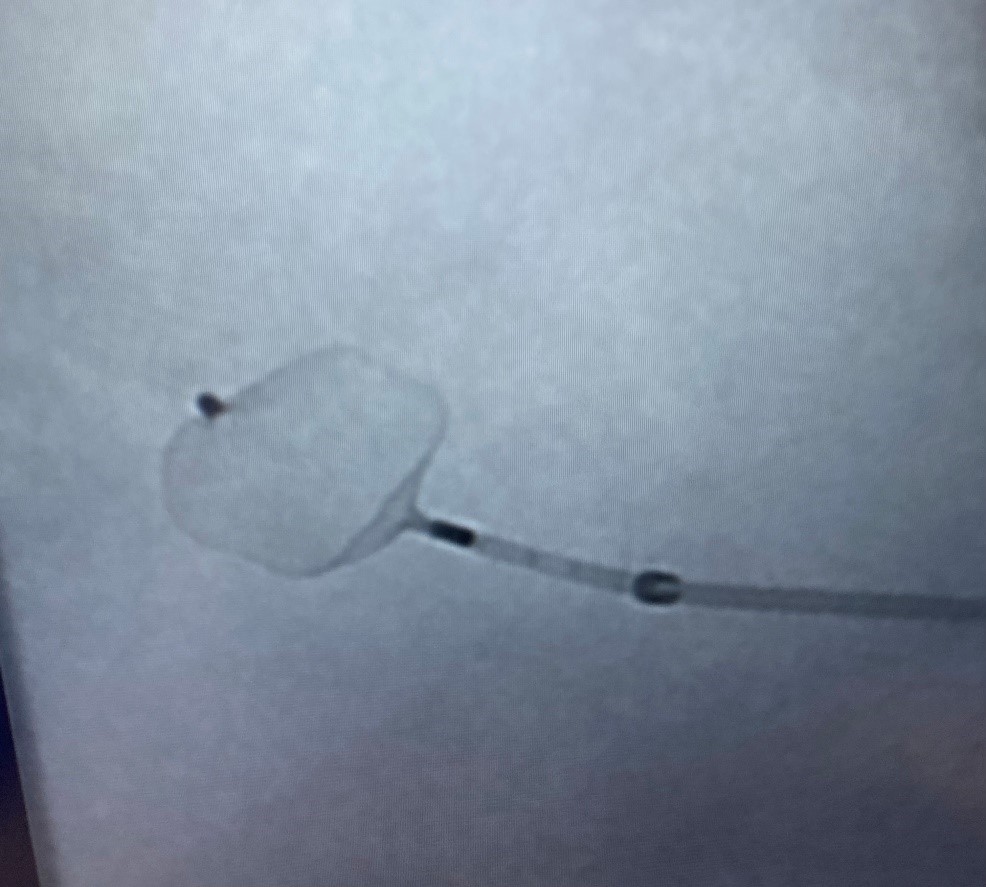

The WEB Device inserted into aneurysm prior to detachment. See how the device fills the aneurysm. an electrical current dissolve a metal junction (arrow) to precisely release the device